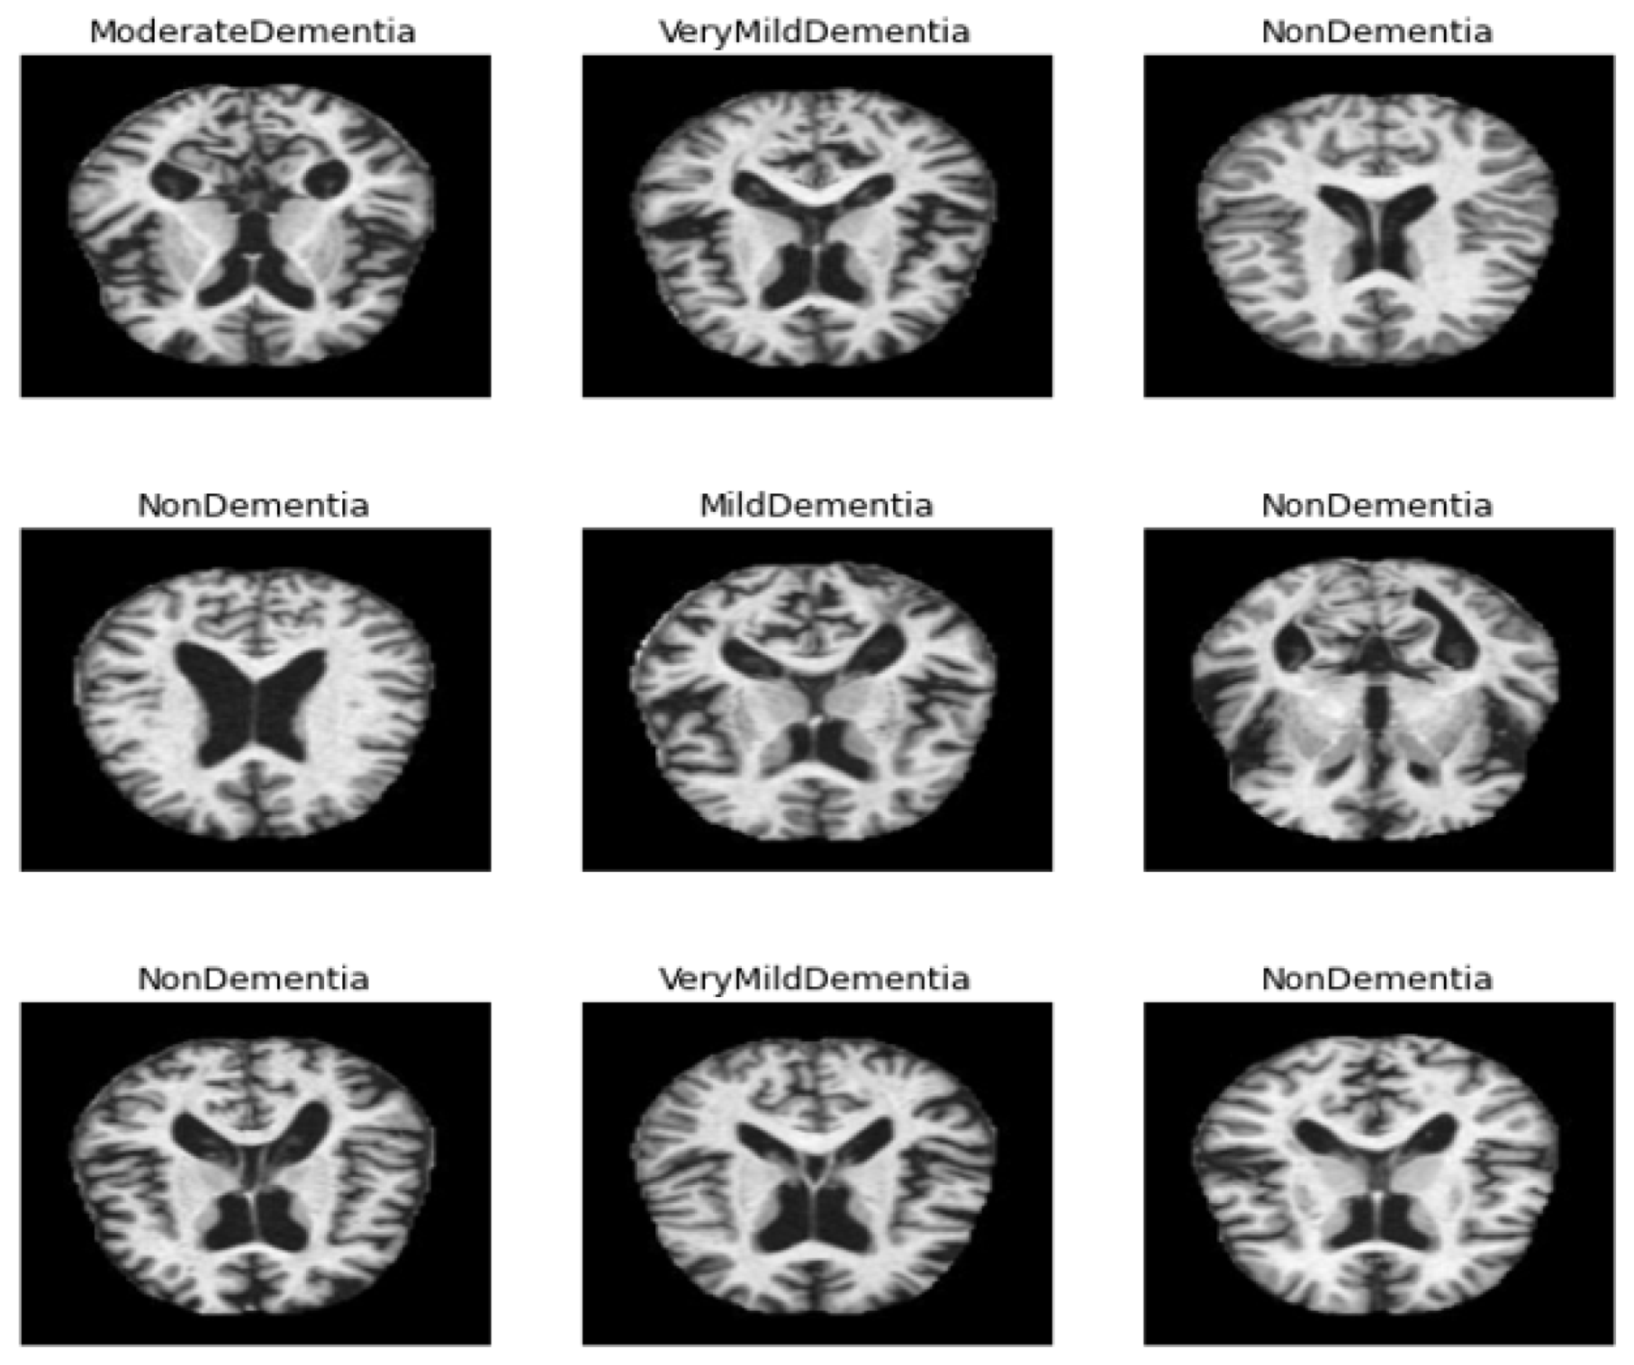

The patient’s position inside the scanner, his motions and images obtained from different locations and many other factors all affected the quality of the MRI images, thereby resulting in a difference in the brightness of the images. The bias field is defined as the difference in MRI intensity values from black to white. Therefore, preprocessing is necessary for the success of the following stages in image processing. Otherwise, if the bias field is not corrected, then all next image processing stages will produce inaccurate results. To achieve reliable accuracy in the next steps, the preprocessing algorithms rectify the failures produced by the bias field and remove the noise. In this study, the Mean RGB colour for MRI scans and image scaling for colour constancy were computed. Finally, the averaging filter was applied to improve the MRI images by computing each central pixel according to the average of neighbouring pixels. Deep learning models were used to resize all MRI images. Figure 3 describes sample MRI images after image enhancement.

Figure 3. Sample MRI images after the image enhancement process.